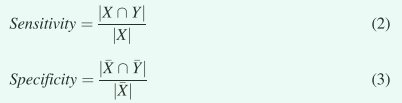

其中X和Y分别是ground truth 轮廓和用所提出的方法获得的轮廓。敏感性和特异性量化了ground truth体积内外的重叠率

灵敏度和特异性量化了ground truth体积内外的重叠率,其中“X”和“Y”分别是ground truth轮廓和自动分割轮廓外的体积。平均表面距离 (MSD) 计算两个有向平均表面距离的平均值,